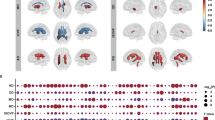

Schizophrenia and bipolar disorder share genetic risk, brain vulnerability, and clinical symptoms. The ZNF804A risk variant, rs1344706, confers susceptibility for both disorders. This study aimed to identify neural mechanisms common to both schizophrenia and bipolar disorder through this variant's potential effects on cortical thickness, white matter tract integrity, and cognitive function. Imaging, genetics, and cognitive measures were ascertained in 62 healthy adults aged between 18 and 59 years. High-resolution multimodal MRI/DTI imaging was used to measure cortical thickness and major frontotemporal and interhemispheric white matter tracts. The general linear model was used to examine the influence of the ZNF804A rs1344706 risk variant on cortical thickness, white matter tract integrity, and cognitive measures. Individuals homozygous for the risk variant (‘A’ allele) demonstrated reduced cortical gray matter thickness in the superior temporal gyrus, and in the anterior and posterior cingulate cortices compared with C-allele carriers. No effect of the risk variant on microstructural integrity of white matter tracts was found. Reduced attention control was found in risk allele homozygotes, aligning with findings in the anterior cingulate cortex. Our data provide a novel, genetically based neural risk mechanism for the major psychoses by effects of the ZNF804A risk variant on neural structures and cognitive function susceptible in both disorders. Our findings link genetic, imaging, and cognitive susceptibility relevant to both schizophrenia and bipolar disorder.